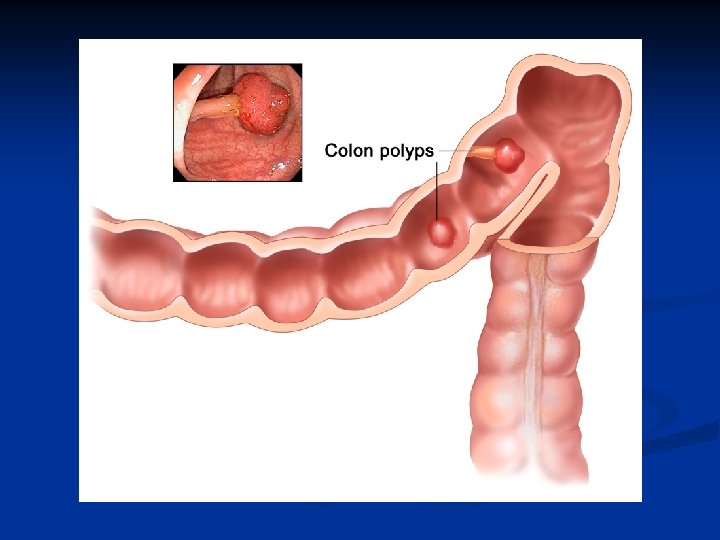

Benign tumors I. n 2 types - tubular adenoma - pedunculated villous adenoma - sessile n They have malignant potential , so they should be removed. Malignancy depends on size and type of adenoma. More dangerous are large and villous adenomas n n

Benign tumors II. Complications - bleeding, - diarrhoe, hypokalaemia / villous / Treatment - fibre endoscopic removal - operation - partial colon resection (very large polyps )